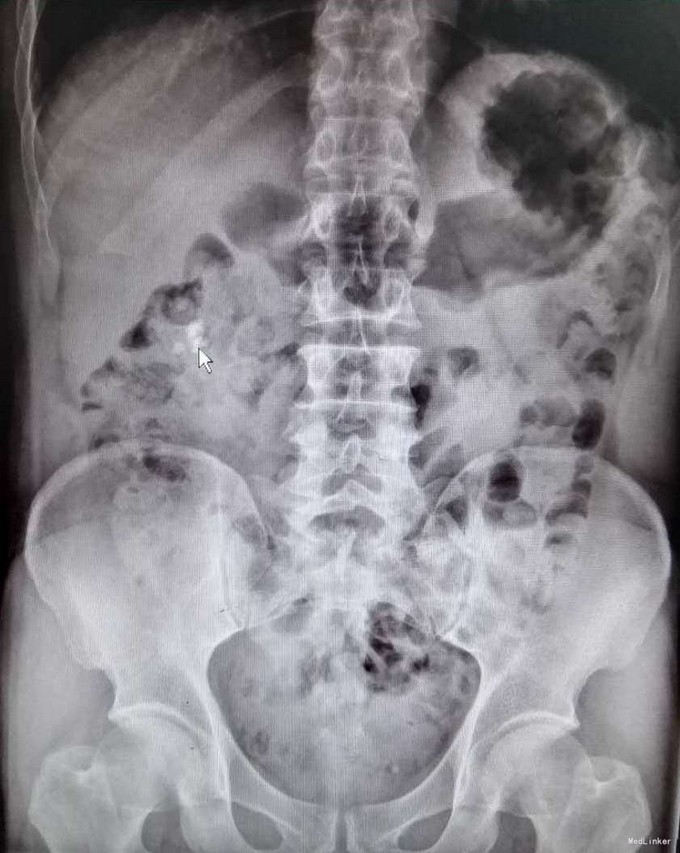

1、患者中年男性,慢性病程,既往有泌尿系结石史 2、患者2年前无明显诱因出现右侧腰部疼痛,疼痛呈放射状,阵发性,无恶心、呕吐,无尿频、尿急,尿痛,无排尿困难,无血尿、脓尿,我院门诊就诊,查KUB提示:右肾多发结石

3、查体:右肾区叩击痛(+),右侧肋脊点、肋腰点压痛(+),余查体未见明显异常 4、辅助检查:我院KUB提示:右肾多发结石,CTU平扫+增强:1、右肾多发结石,右肾下极局限性萎缩2、双肾多发囊张,3、肝多发囊肿